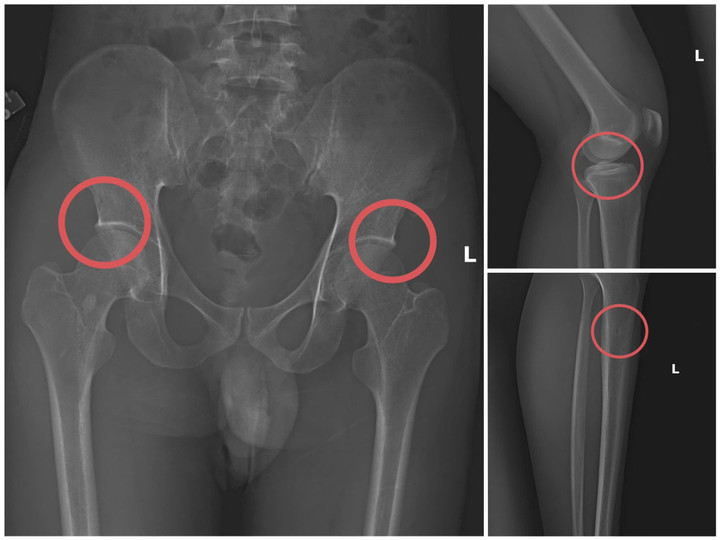

Cựu cán bộ y tế cầm đầu đường dây tự đánh vỡ xương trục lợi 6 tỷ đồng bảo hiểm- Ảnh 2.

Bản phim chụp XQ một số tổn thương xương do đối tượng tạo ra. (Ảnh: Công an tỉnh Phú Thọ).

Đáng chú ý, Châu trực tiếp thực hiện hành vi tiêm thuốc mê, rồi dùng kim tiêm, búa... để tác động vào xương người mua bảo hiểm, tạo nên các vết nứt, vỡ xương tương tự tai nạn thật.

Theo đánh giá của Giám đốc Công an tỉnh, thủ đoạn này vừa tàn nhẫn, vô nhân tính, coi thường sức khỏe, tính mạng của người tham gia, vừa được tính toán kỹ để gây thương tích đúng vị trí có mức chi trả cao, khiến các công ty bảo hiểm khó phát hiện dấu hiệu gian dối.